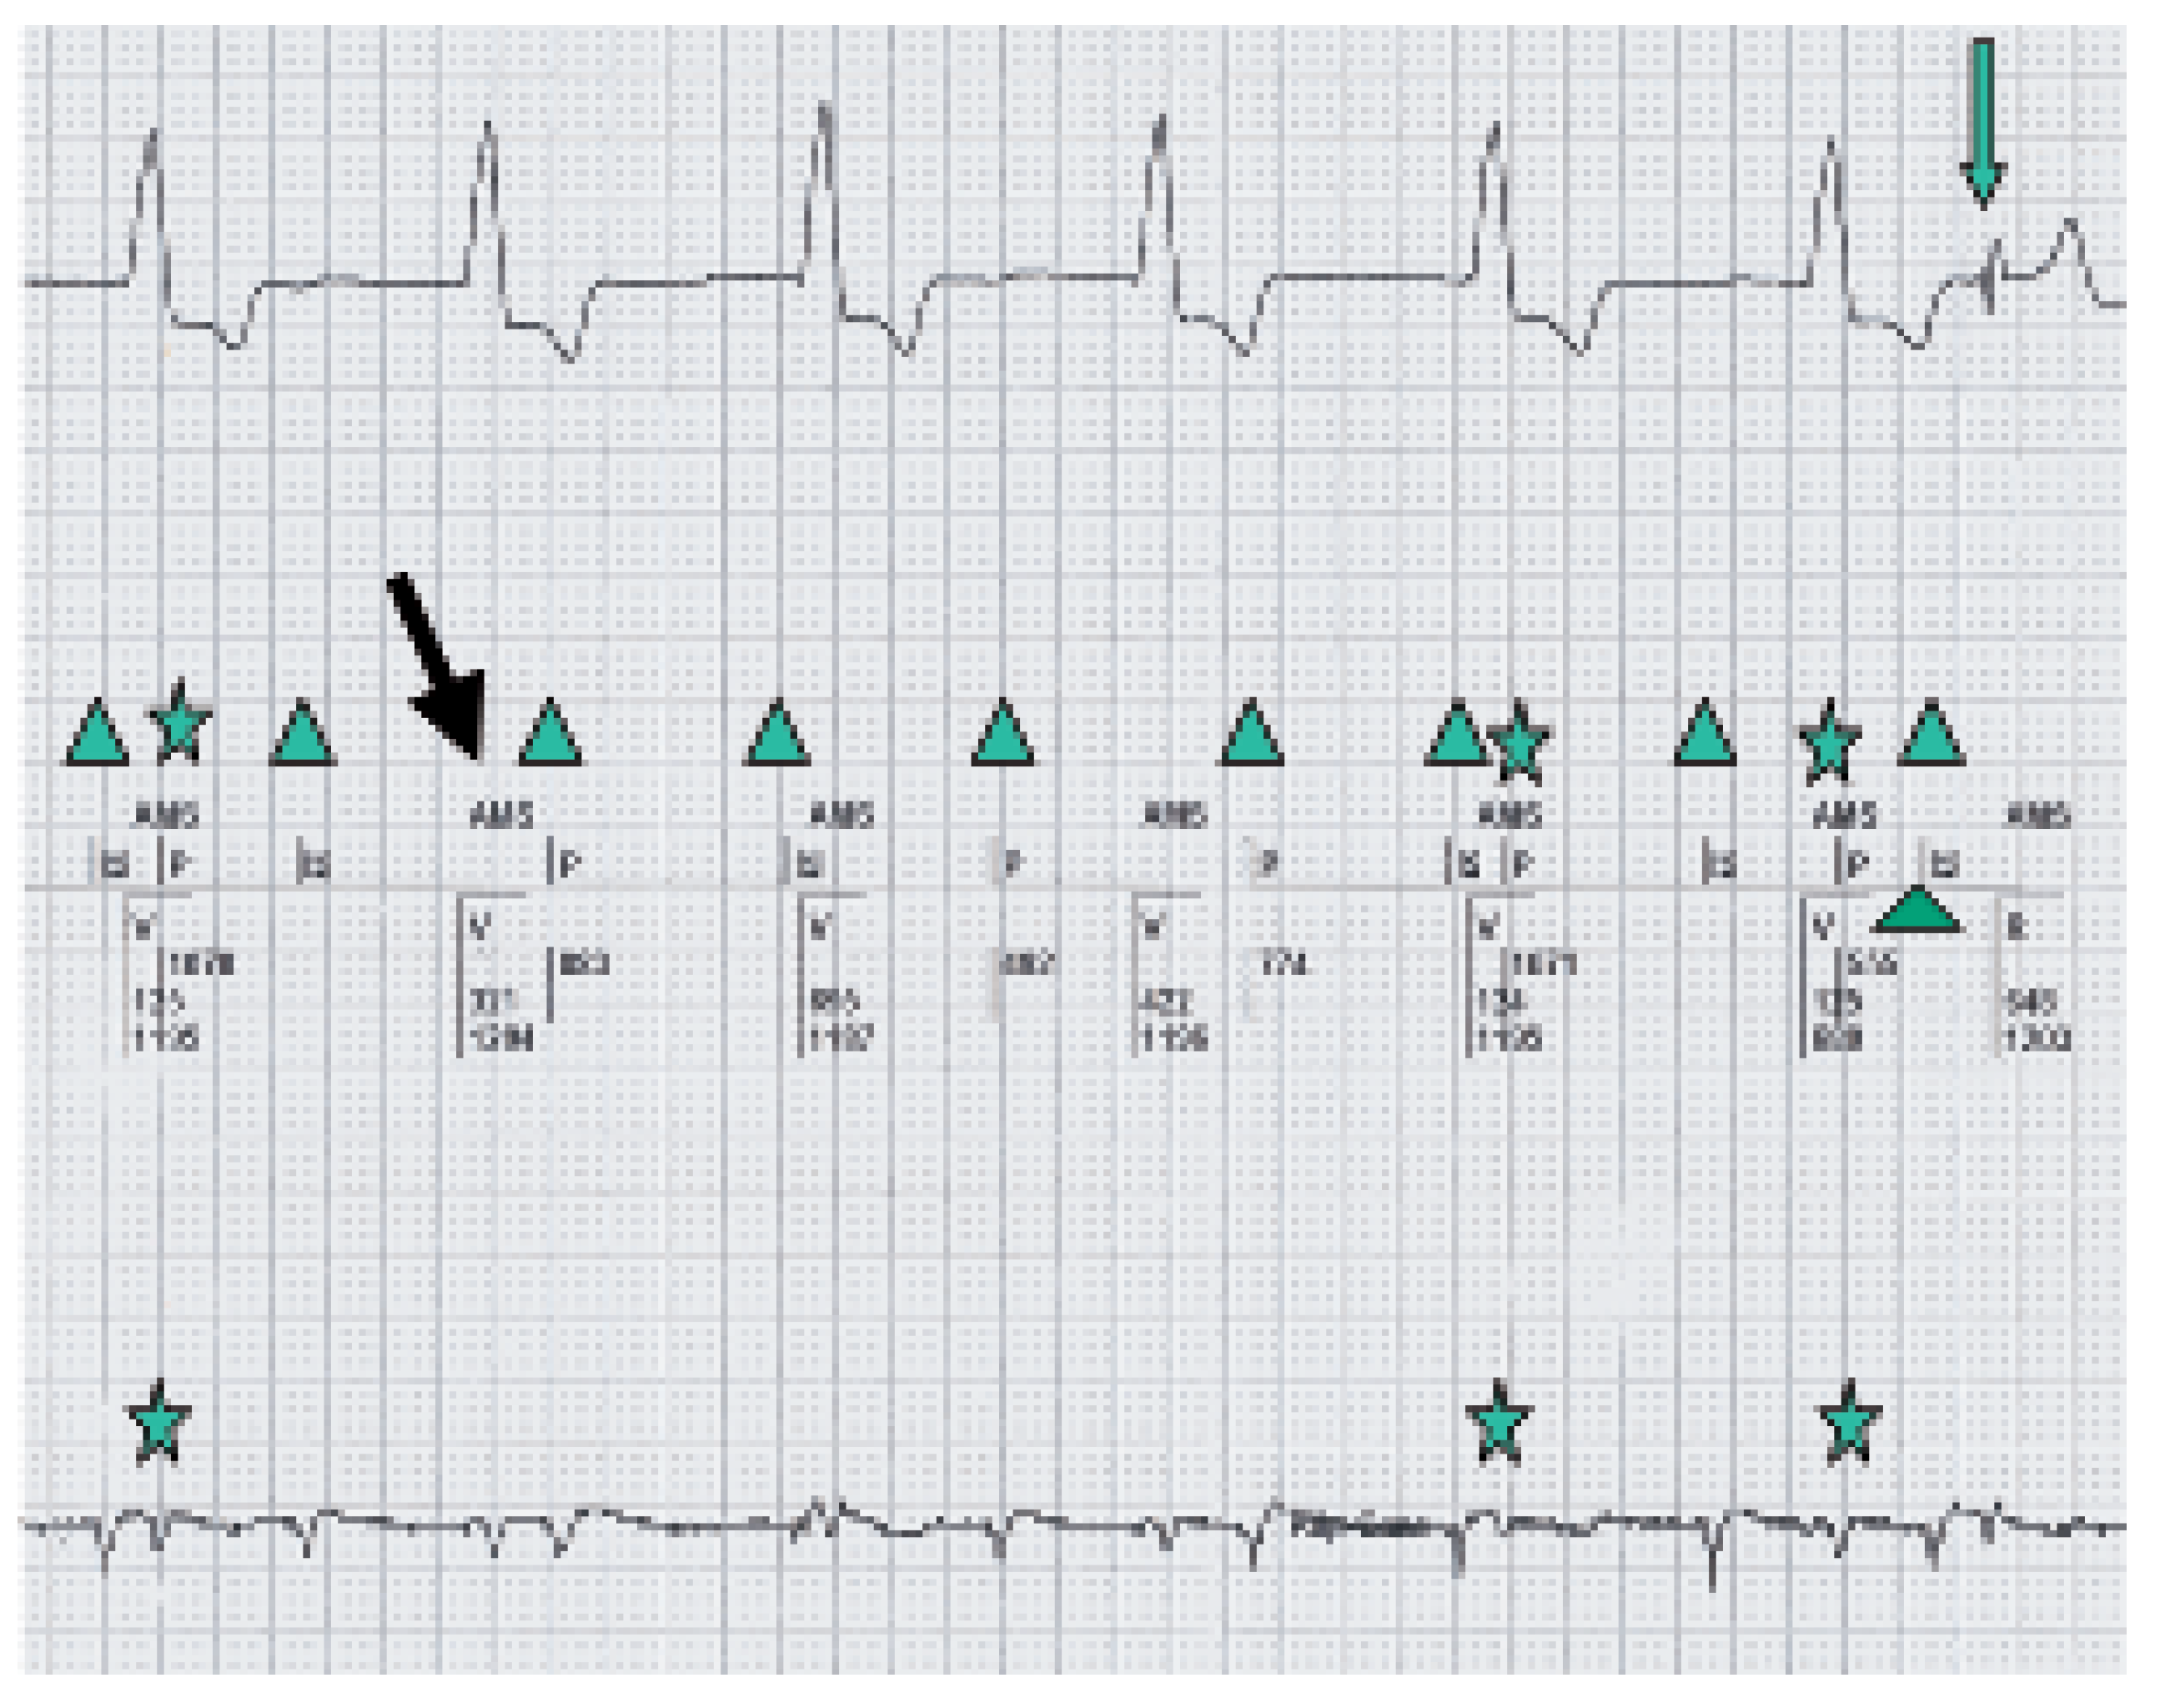

AMS with VVI back up mode is shown.

P-waves noted in the marker channel (middle line).

Intermittent Far Field sensing seen in the bottom line (signal measured between Atip

and Aring) and in the marker channel (middle line).

Intrinsic ventricular beat.